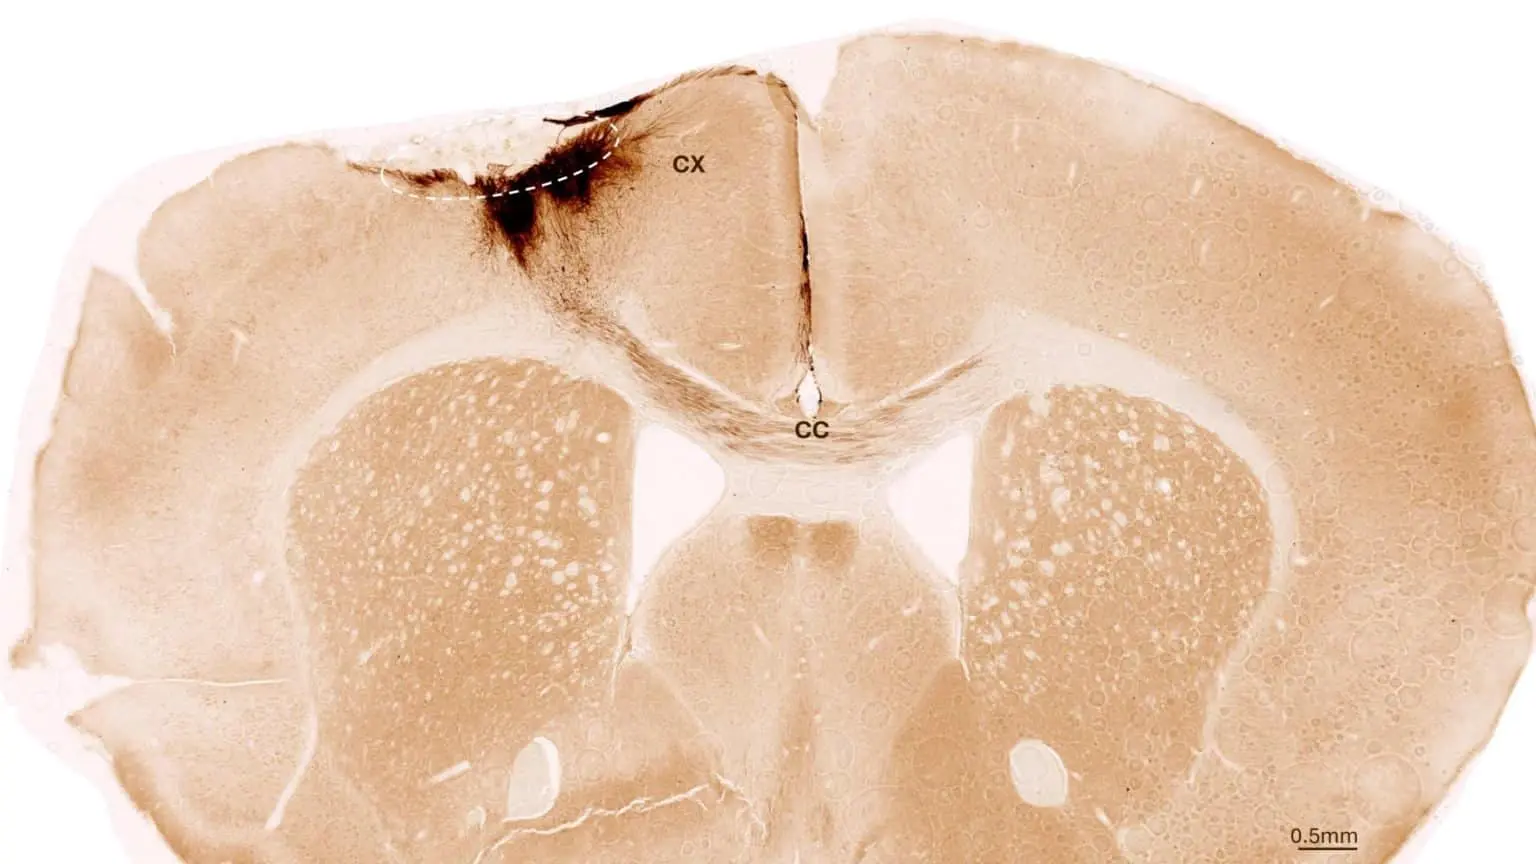

Спустя неделю после инсульта ученые ввели стволовые клетки в поврежденный участок мозга. Применяя комплекс визуализирующих и биохимических методов, они отслеживали результаты. Наблюдения в течение пяти недель показали, что трансплантированные клетки не только выжили, но и большинство из них превратилось в функциональные нейроны, интегрировавшиеся в существующую мозговую сеть.

Были зафиксированы и другие признаки восстановления: формирование новых кровеносных сосудов, снижение воспаления и укрепление гематоэнцефалического барьера. Важнейшим результатом стало устранение двигательных нарушений, вызванных инсультом.